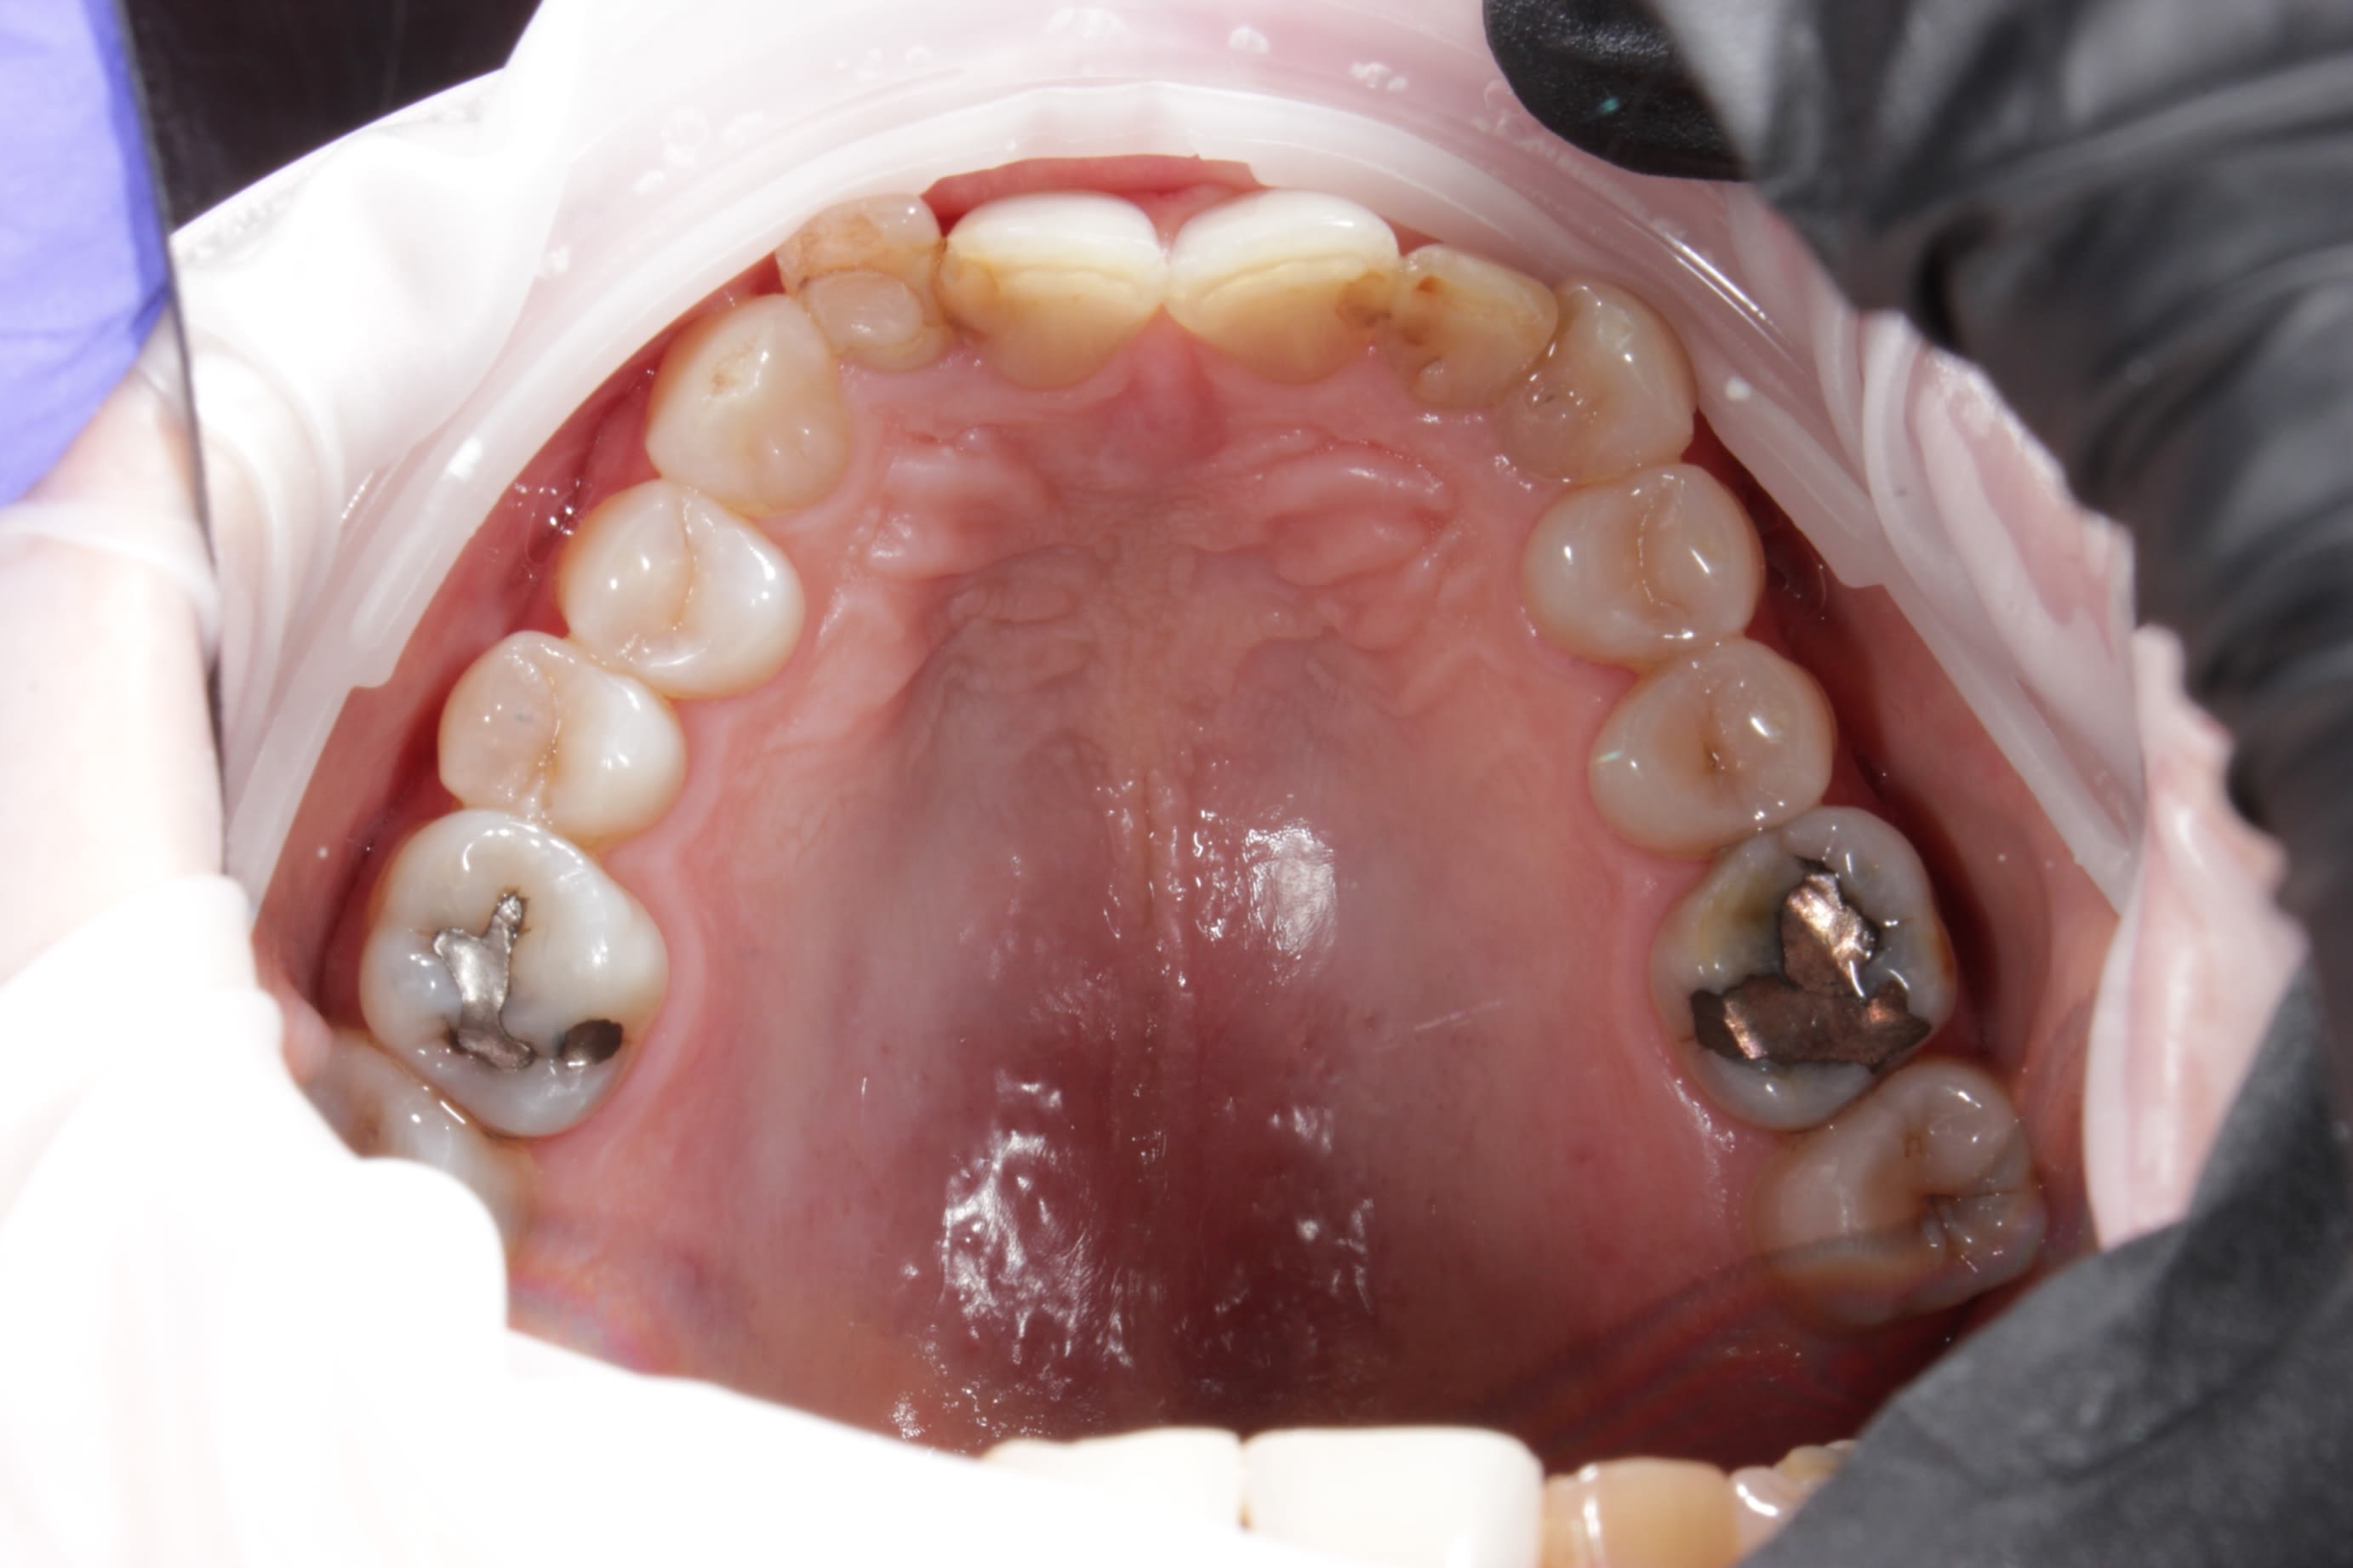

photos